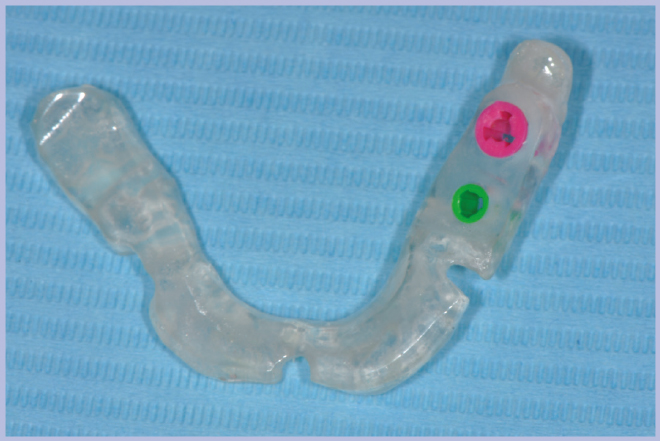

Viene quindi richiesto al tecnico di modificare in laboratorio la mascherina radiologica mediante il posizionamento delle boccole di guida adatte agli impianti da posizionare (Exacone® 6.5 e Exacone® 3,3×8) in asse con gli analoghi del modello Master 3D ed eliminando il repere radiologico standardizzato, trasformandola così nella dima chirurgica (Figg. 14, 15). Si procede quindi alla prova della mascherina sulla paziente per verificarne la stabilità e la corrispondenza esatta con il modello Master 3D (Fig. 16). La seduta chirurgica con tecnica flapless, guida chirurgica e Frese Zero1 dedicate non presenta alcuna difficoltà ; al termine dell’inserimento si posizionano sugli impianti tappi di guarigione bassi per permettere loro di guarire con tecnica sommersa (Figg. 17-27). Si effettua nella stessa seduta una CBCT che dimostra che la posizione clinica degli impianti risulta sovrapponibile a quella progettata dagli Autori (Figg. 28-30).

- Figg. 14, 15 – Trasformazione della dima radiologica in dima chirurgica sul modello Master 3D

- Fig. 15